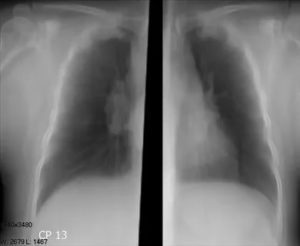

Врач-рентгенолог визуально отличает на фотопленке изменения в плотности тканей легких. Те места, где плотность выше, чем у здоровых легких, свидетельствуют о каких-то проблемах в тканях. Соединительная ткань, разрастаясь, замещает легочную ткань и на флюорографии выглядит более светлыми участками.

Различают спайки, фиброзы, наслоения, тени, склерозы, тяжистости, лучистости, рубцовые изменения. Все эти аномалии, если они присутствуют, видны на снимках легких.

Усиление сосудистого или лёгочного рисунка

Лёгочный рисунок это тени на флюорограмме, «отбрасываемые» венами и артериями, пронизывающими легкие. Его еще называют сосудистый рисунок. Если в результатах написан такой пункт, то это значит, что в каком-то отделе легких имеется область, в которую более интенсивно поступает кровь по артериям.

Фиксируется при каких-то острых воспалительных процессах, бронхитах, пневмониях, а также может свидетельствовать о пневмоните, и требует повторного снимка, чтобы убедиться, что нет онкологии.